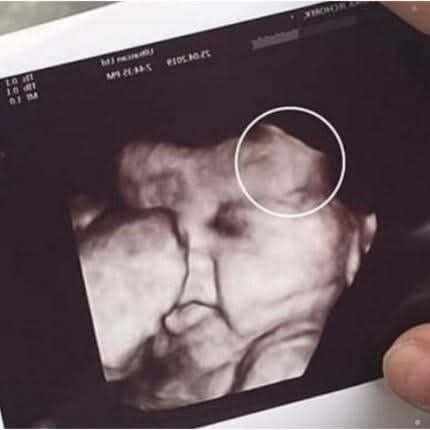

Mother is scared to see her daughter’s ultrasound; image showed the… See more

routine prenatal checkup took an unexpected turn for one mother after she grew visibly anxious during her daughter’s ultrasound appointment. According to witnesses at the clinic, the

mother had accompanied her daughter for support but became increasingly uneasy as the technician prepared to reveal the scan. What was supposed to be a joyful moment quickly shifted into uncertainty when the medical staff paused to take a closer look at the monitor.

technician, maintaining calm professionalism, informed the family that the image had shown something unusual that required further evaluation. While they did not immediately disclose details, the brief silence in the room left both mother

and daughter unsettled. Staff assured them that unclear images are common—ultrasounds can sometimes capture shadows, angles, or movements that look concerning but turn out to be harmless upon review READ MORE BELOW